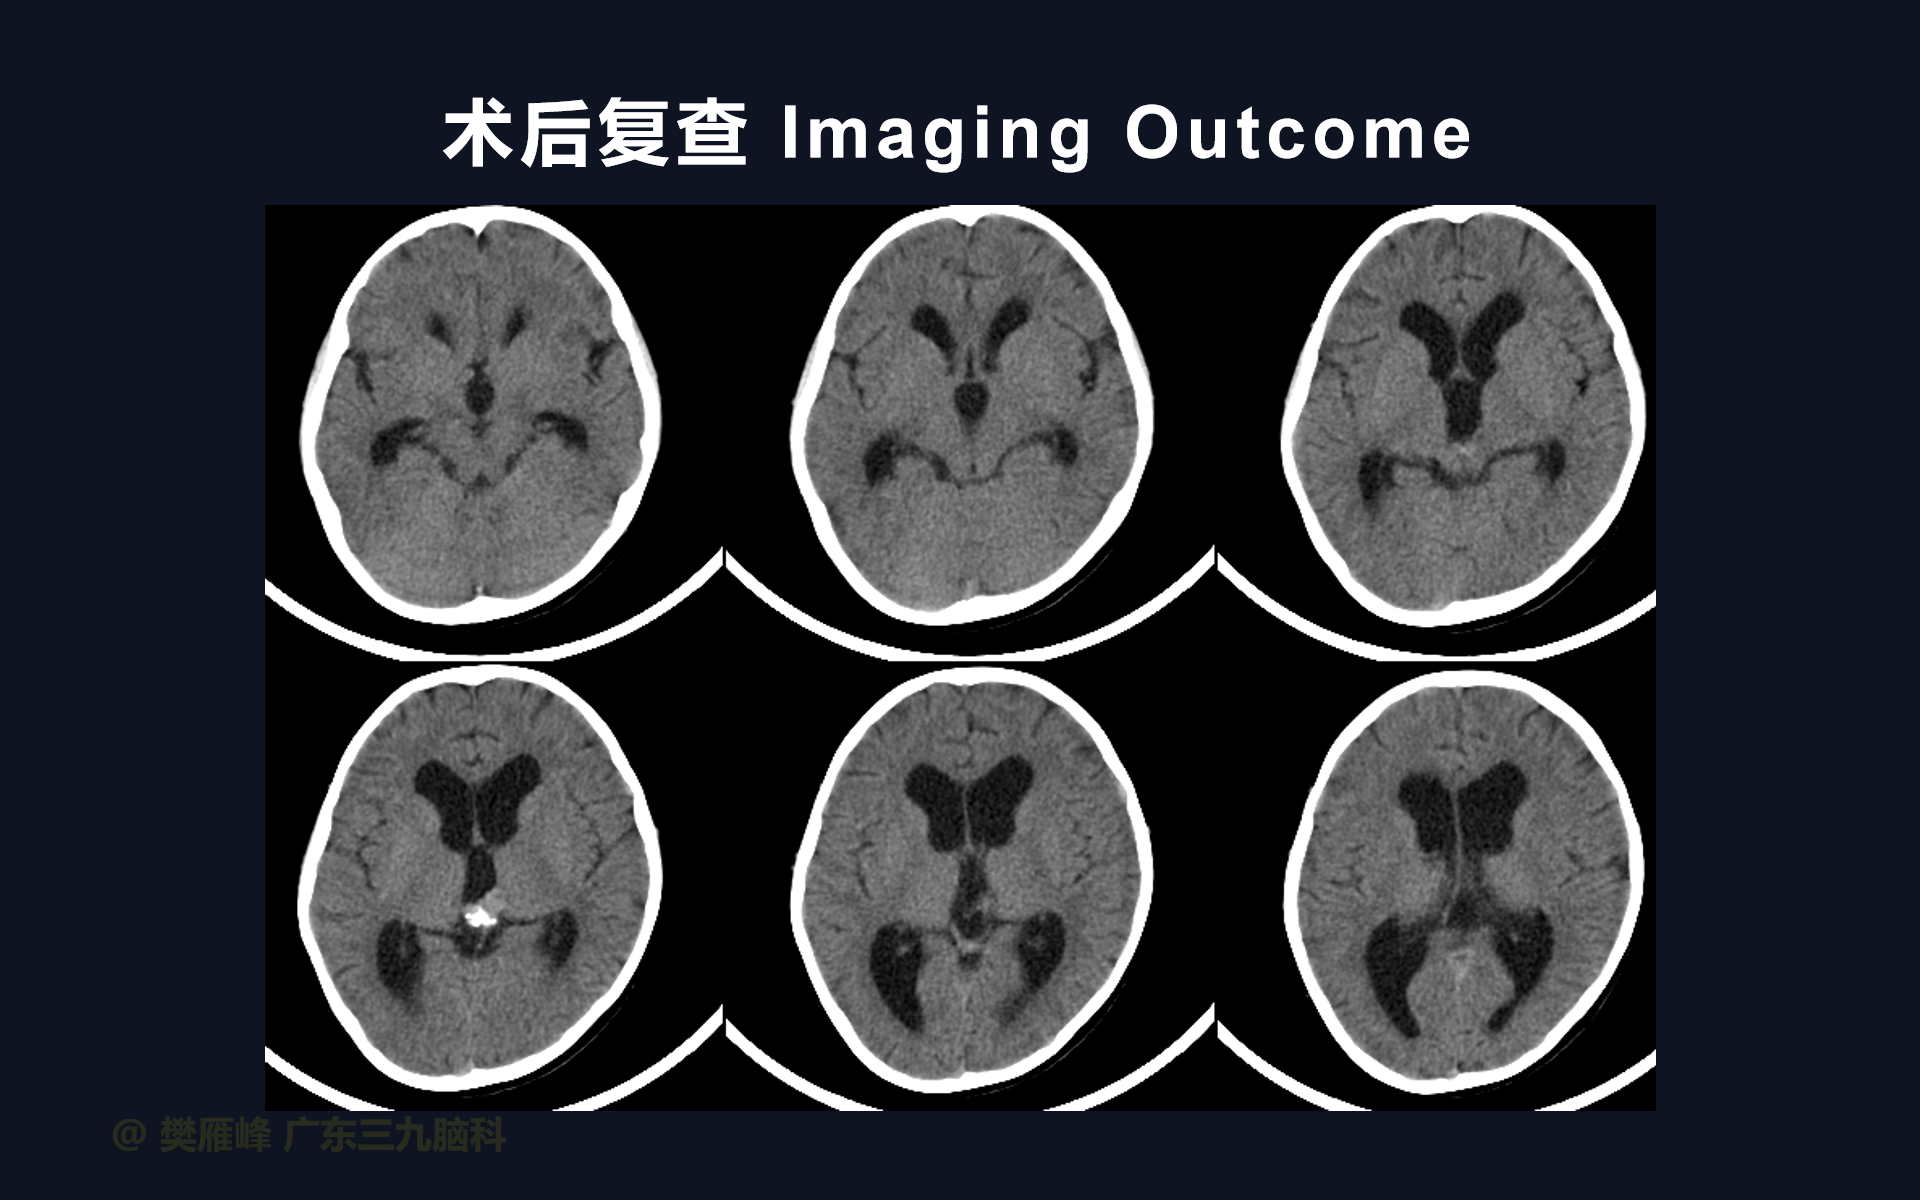

在这个二维手术视频中,展示了2例神经内镜下三脑室底造瘘+活检治疗三脑室后部肿瘤的方法。患者均为三脑室后部病变导致的梗阻性脑积水,病理结果1例为生殖细胞瘤,1例为淋巴瘤,在经过术后的放化疗病情均得到控制,生活质量满意。我们展示了安全的病变活检和第三脑室造瘘的技术要点,以最大限度减少术后继发脑积水和早期并发症。